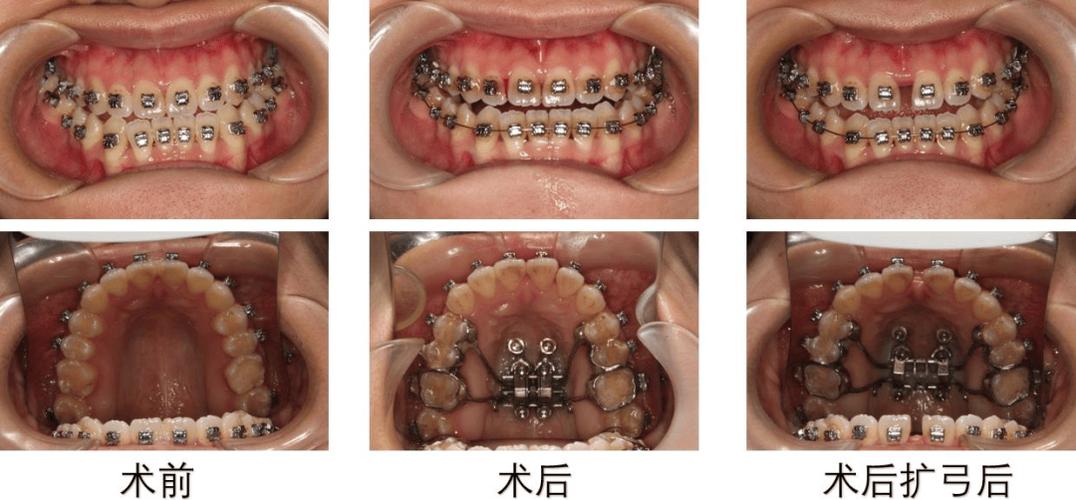

(图片来源网络,侵删)- 每4-6周复诊一次,检查牙齿移动情况、口腔卫生及弓丝稳定性。